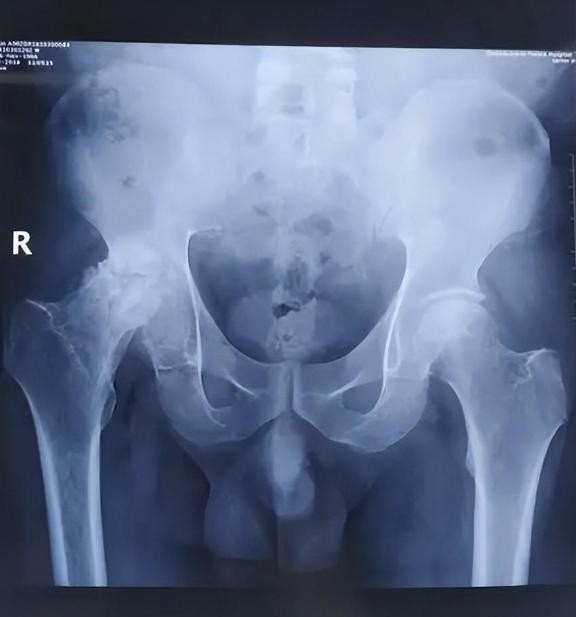

真正的突破出现在X光检查中。当影像出现在屏幕上时,放射科医生惊讶地发现,村民们的股骨头竟然消失了!

正常人的髋关节应该有一个球状的骨头与骨盆相连,但这些村民的大腿骨直接与骨盆融合在一起。这种异常的骨骼结构解释了为什么村民们走路时总是摇摇晃晃的。